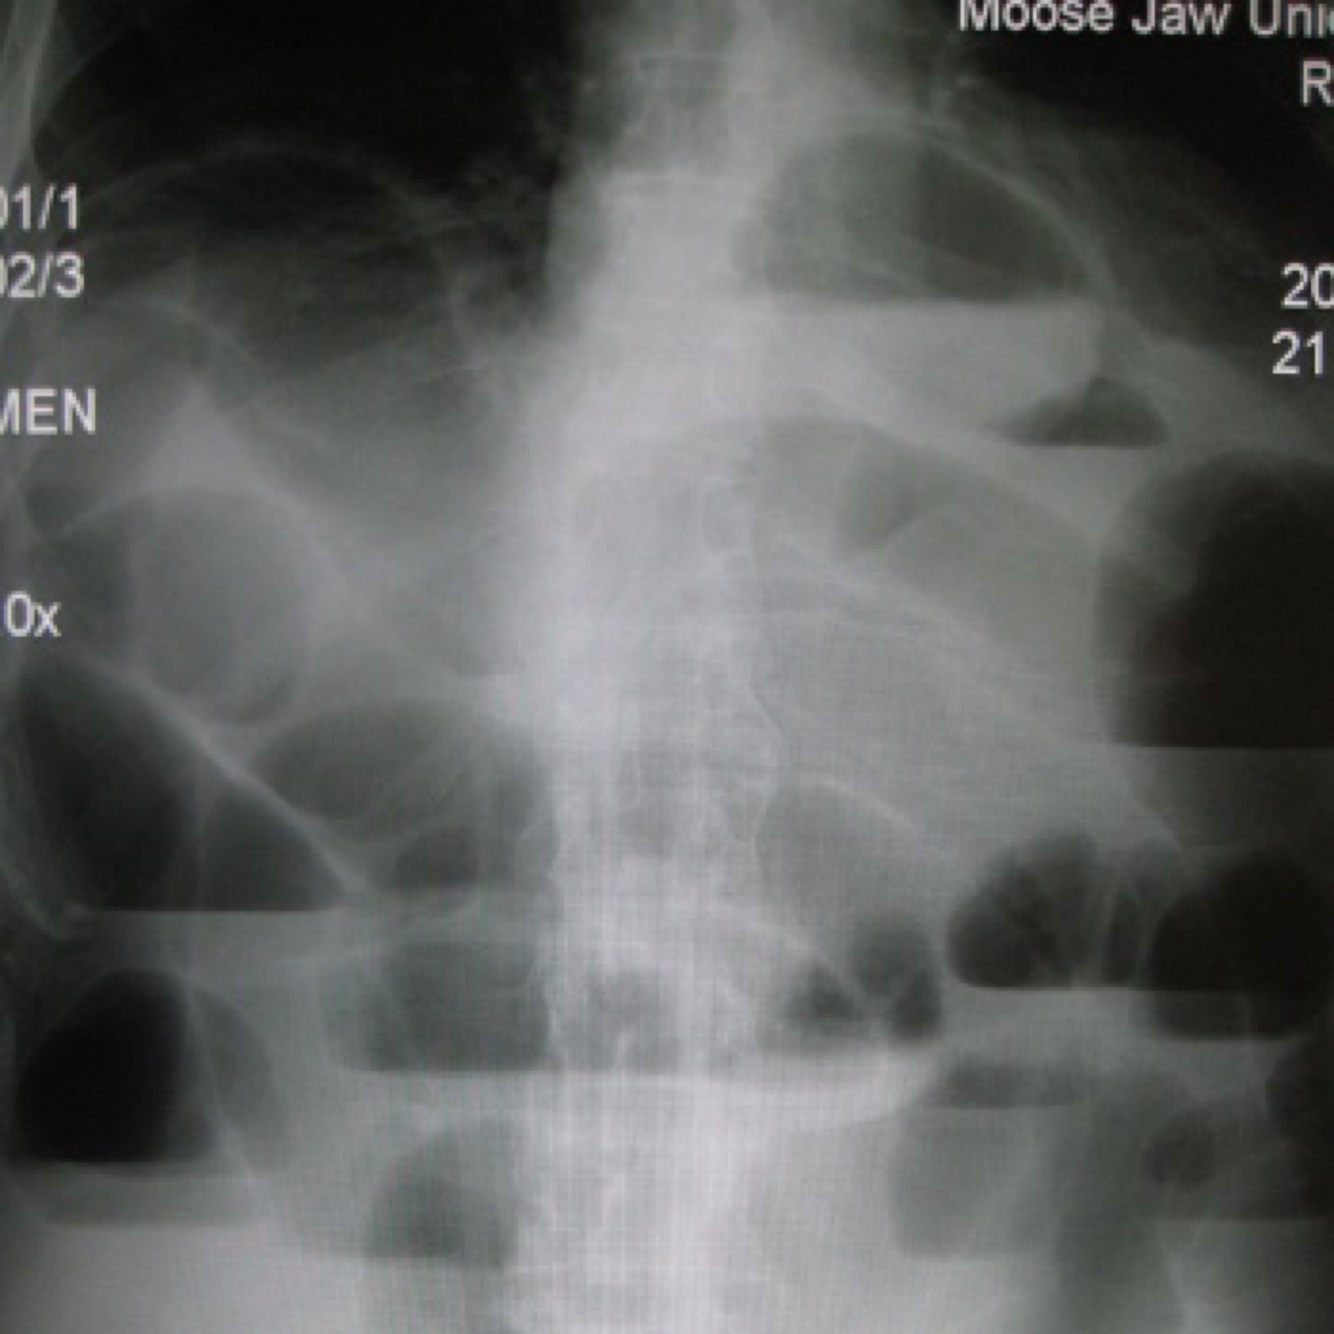

small bowel obstruction. Dilated loops of small intestine, seen in the x-ray image of the abdomen,